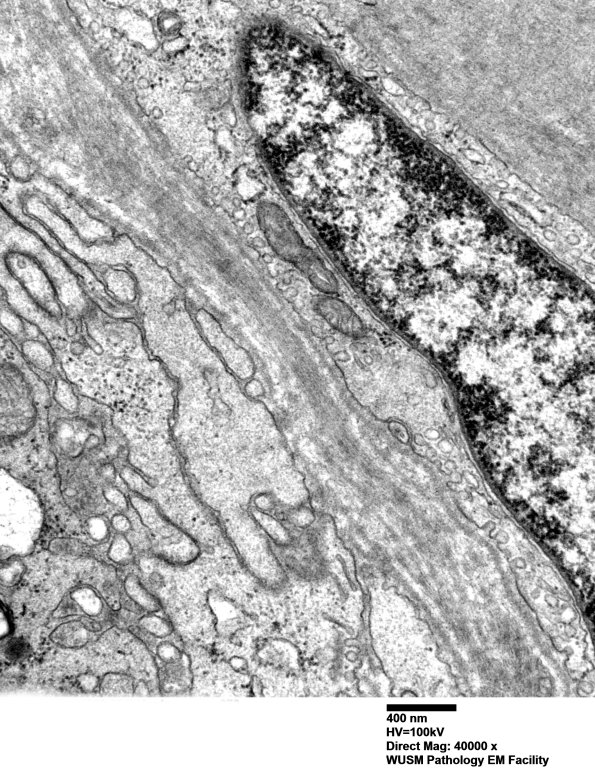

The origin of these processes appears to be from the perineurial cells themselves. (electron micrographs)